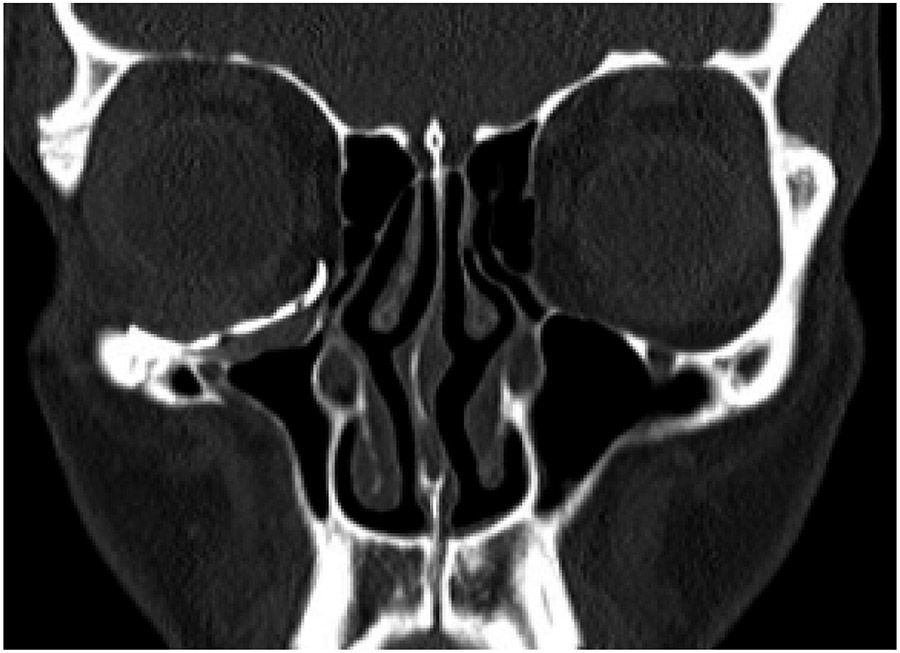

The patient underwent a Caldwell-Luc approach and concurrent orbital floor reconstruction. A one-stage approach was chosen for a faster recovery and single surgery. Correction of enophthalmos and dystopia was performed using a patient-specific CAD/CAM implant (Fig. 3) assisted by intraoperative navigation and CT scan (Fig 4.). The 0.3mm orbital floor titanium plate was placed through a transconjunctival approach (Fig. 5). The patient was found to be complaint free and full recovered at 6th-month follow-up (Fig 1.).

Moreover, virtual surgical planning can offer the surgeon a better understanding of the anatomy. Intraoperative navigation and CT intraoperative control, add extra safety and greater accuracy to the procedure, controlling ideal positioning of the implant and avoiding complications regarding optic nerve damage. The use of intraoperative navigation has been shown to offer a significantly better orbital volume and eyeball projection, without increasing surgery duration. Customized titanium implants accurately reproduce orbital contours thus restoring orbital volume. This reduces operative time and improves the functional and aesthetic outcomes of post-traumatic orbital reconstruction.